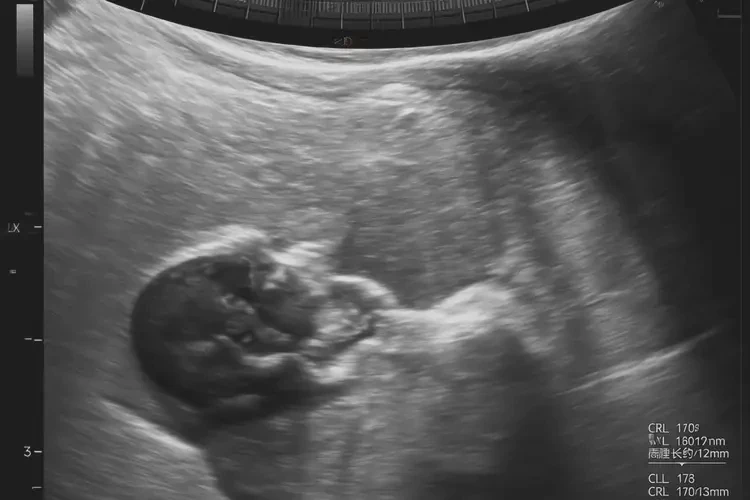

胎心率在孕7周6天时约为110次/分钟,属于正常范围。

在孕7周6天时,胎儿的胎心率通常在100-170次/分钟之间波动,因此110次/分钟左右的胎心率是正常的。胎心率会受到多种因素的影响,包括胎儿的活动水平、孕妇的情绪和身体状况等。以下是关于孕7周6天胎心率的详细信息:

- 正常范围:在孕早期(孕7周6天属于孕早期),胎心率的正常范围通常在100-170次/分钟之间。随着孕周的增加,胎心率会逐渐下降,到孕晚期时,正常范围通常在110-160次/分钟之间。